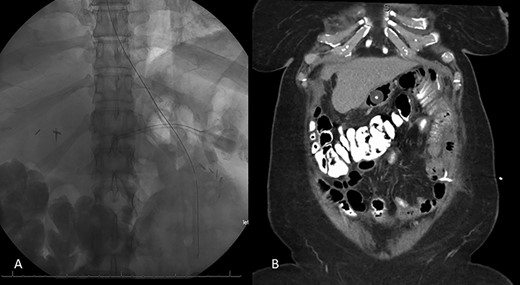

Decision was made to explore and attempt to excise the infarcted omentum. She was taken to the operating room and underwent a diagnostic laparoscopy. However, due to the large size of the omental infarction with an encapsulated necrotic liquefied, purulent secretion and significant adhesions, we decided to convert it to a midline laparotomy. We then proceeded with resection of right-sided infarcted, necrotic, liquefied omentum and abdominal washout (Fig. 3). Culture from the purulent secretion that was inside encapsulated omentum grew Streptococcus anginosus. She received Meropenem and Fluconazole. She had a prolonged and protracted recovery with a transient kidney injury and the development of multiple intra-abdominal (inter-loop, peri-hepatic, peri-splenic and pelvic) fluid collections (Fig. 4A). These collections were treated by percutaneous drainage (pelvis × 1, perisplenic and left-sided collections × 2). Three weeks from the take back, she developed a small bowel obstruction with significant dilation of the biliopancreatic limb and excluded stomach (Fig. 4B and C). She was taken to the operating room and had an endoscopically placed nasogastric tube just passed the jejunojejunostomy. Then, she underwent CT-guided gastrostomy tube to decompress in the gastric remnant (Fig. 5 A and B). One week after the rendezvous nasogastric and gastric remnant decompression, an oral and through the G-tube contrast study demonstrated patency of the gastrojejunostomy and resolution of the small bowel obstruction (Fig. 6). The patient was discharged home on POD #39 tolerating a regular postbariatric surgery diet.

A: Abdominal and pelvic CT scan obtained at POD # 29. From index RYGB and POD # 8 from excision of infarcted omentum showing loculated perisplenic, pelvic and perihepatic fluid collections. B and C: Abdominal and pelvic CT scan obtained at POD # 20 from take back and plain X-ray showing gaseous distention of the excluded stomach and duodenum, confirming a small bowel obstruction of the biliopancreatic limb.

Resolution of small bowel obstruction. A: Plain X-ray at POD # 25 from take back showing endoscopically placed nasogastric tube placement near JJ anastomosis B: Abdominal and pelvic CT scan showing percutaneous gastrostomy tube within the excluded stomach and pigtail catheter in the left hemiabdomen.